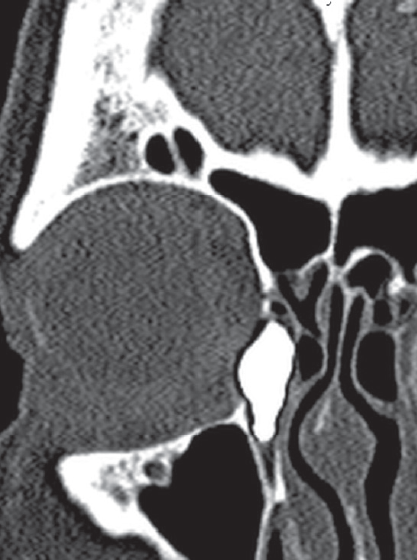

All the patients underwent multislice spiral computed tomography (MSCT) of the middle zone of the face with a contrast of the tear-removing system. The contrast was made using a standard method with a water-soluble radiopaque substance “Omnipak” 320 mg I/ml. MSCT was made on the multislice spiral computer tomographs Phillips Brilliance 64 (Phillips, USA) and TOSHIBA AQULION PRIME in a spiral scanning mode with a slice thickness of 0.6–0.9 mm. A positioning was carried out by laser marks with the patients lying on their back with a standard headrest, and the view is directed straight. The anatomical area of the scan was determined by the tomogram (surview), during the initial examination with the capture of the entire skull. The slices were parallel to the solid sky. According to the results of the MSCT dacriocystography, the degree of patency of the lacrimal pathways, the location of the tear outflow disorder and pathological changes in the lacrimal sac, possible deformity of the facial bones, and changes in bone structures and soft tissues were evaluated [8, 9] (Fig. 4, 5).

Fig. 4. MSCT – dacryocystorhinography. Ectasia of the lacrimal sac. Deviation of the nasal septum